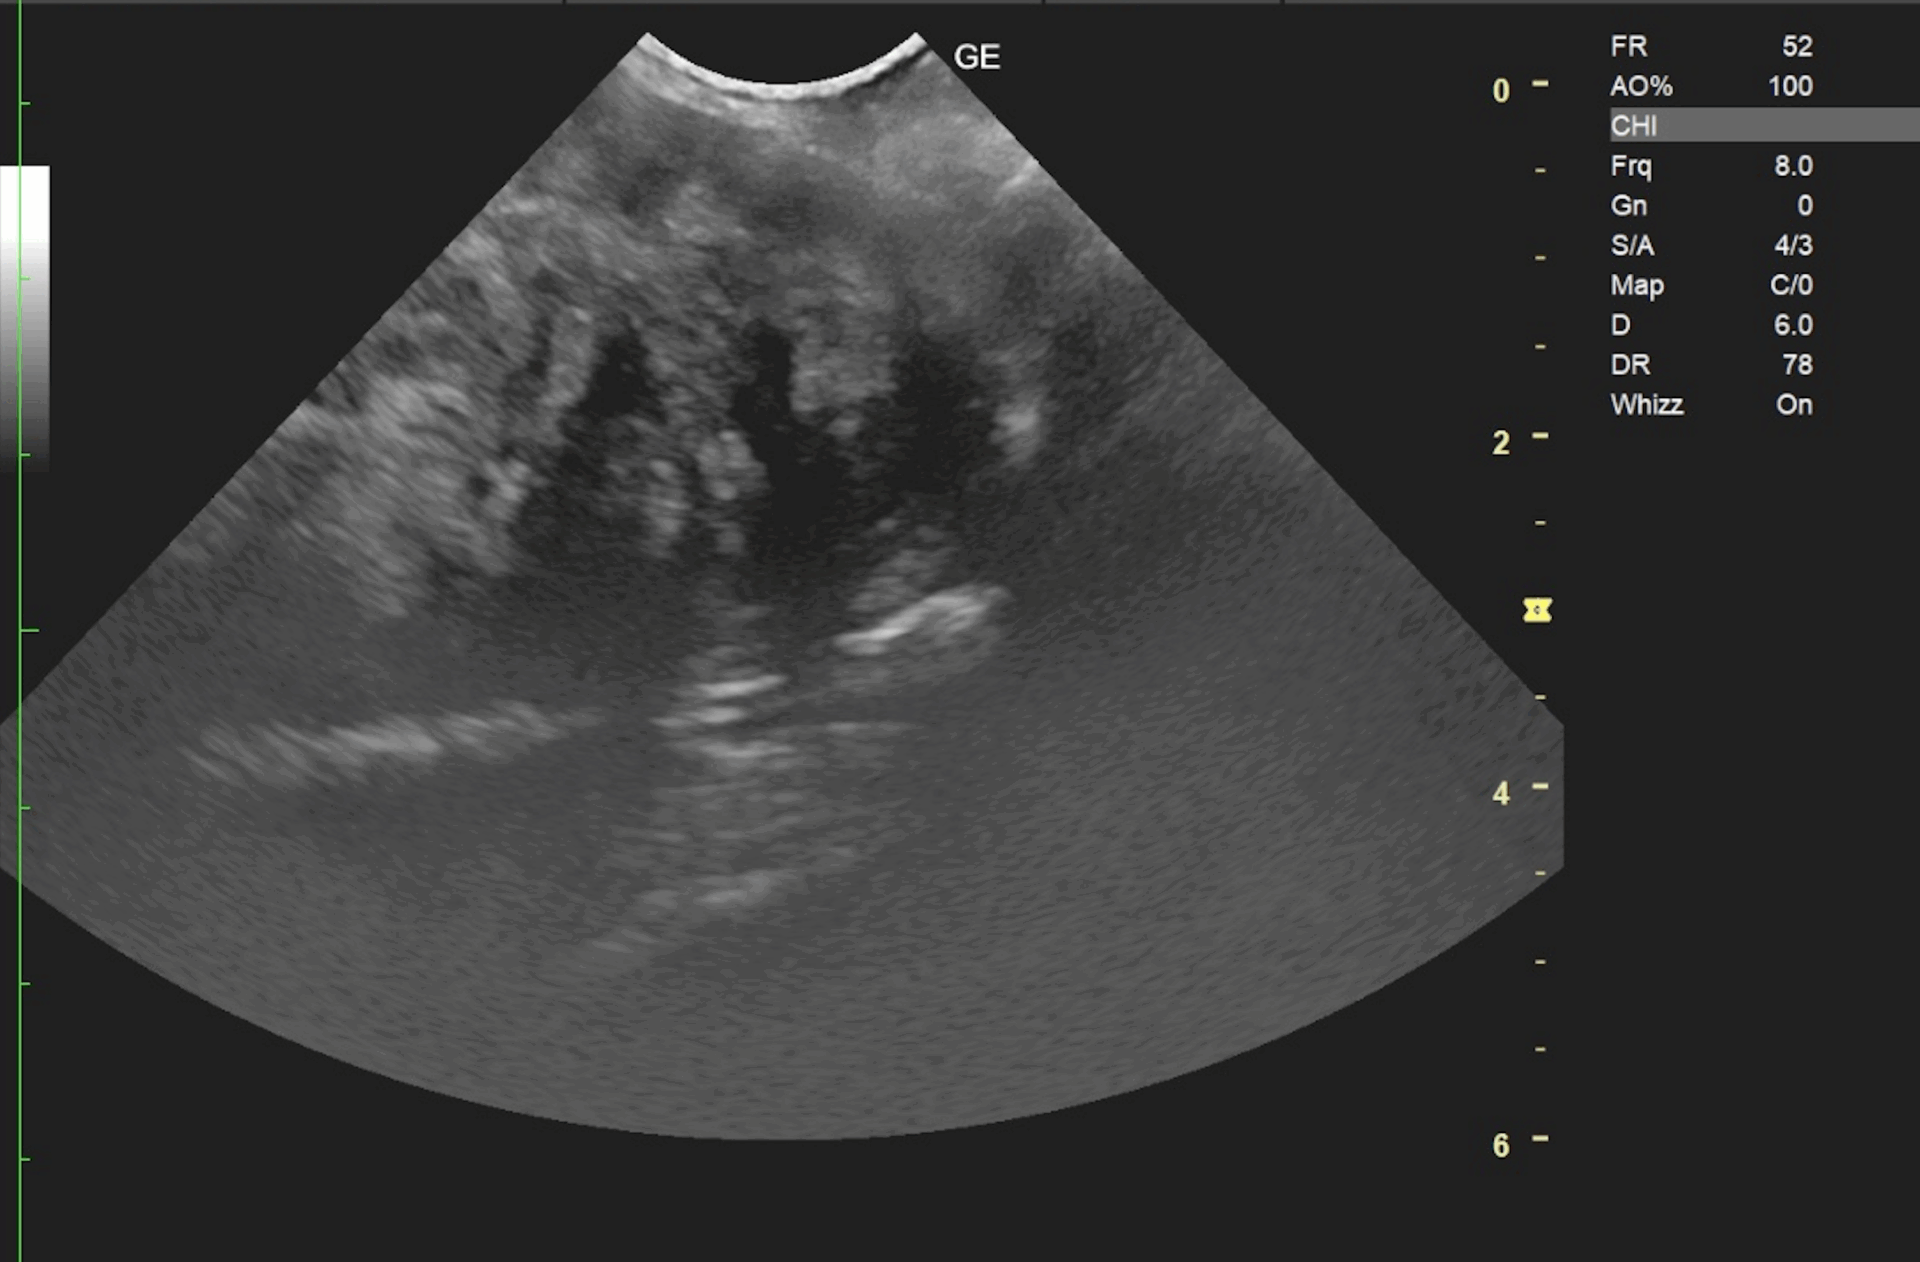

腹部超音波検査にて膣部に境界明瞭な充実性の腫瘤と子宮の液体貯留が認められました。超音波ガイド下の針生検では間葉系細胞が採取されました。

超音波検査、針生検により平滑筋腫が疑われました。飼い主様には念の為にCT検査のためのご紹介をご提示しましたが希望されず、試験開腹による摘出手術を行いました。